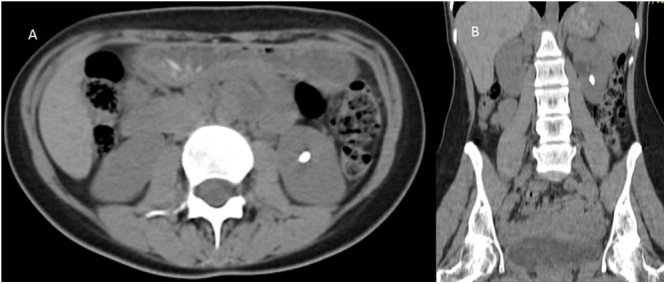

Case presentation: A 23-year-old female presented with acute left flank pain, imaging for which revealed a calculus in the left proximal ureter. A repeat imaging after a few weeks of medical management revealed a calculus of the same dimension at the lower pole calyx of the left kidney, with no calculus present at the initial site, indicating retrograde migration of the calculus. The patient subsequently underwent extracorporeal shockwave lithotripsy with complete stone clearance.